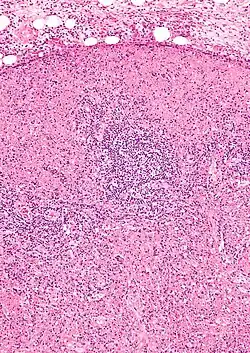

![]() Microfotografia de un nódulo linfático de un paciente afectado por la enfermedad de Kikuchi-Fujimoto. Existen áreas de necrosis y abundantes histiocitos. | ||

Para realizar el diagnóstico, la prueba clave es la biopsia de uno de los ganglios afectados, que muestra hallazgos microscópicos característicos, principalmente áreas de necrosis que distorsionan la estructura del ganglio y la presencia de numerosos histiocitos en las zonas limítrofes de las áreas con necrosis, con escasa presencia de polimorfonucleares neutrófilos y células plasmáticas. Con base en estos hallazgos la enfermedad ha sido denominada linfadenitis histiocítica necrosante.